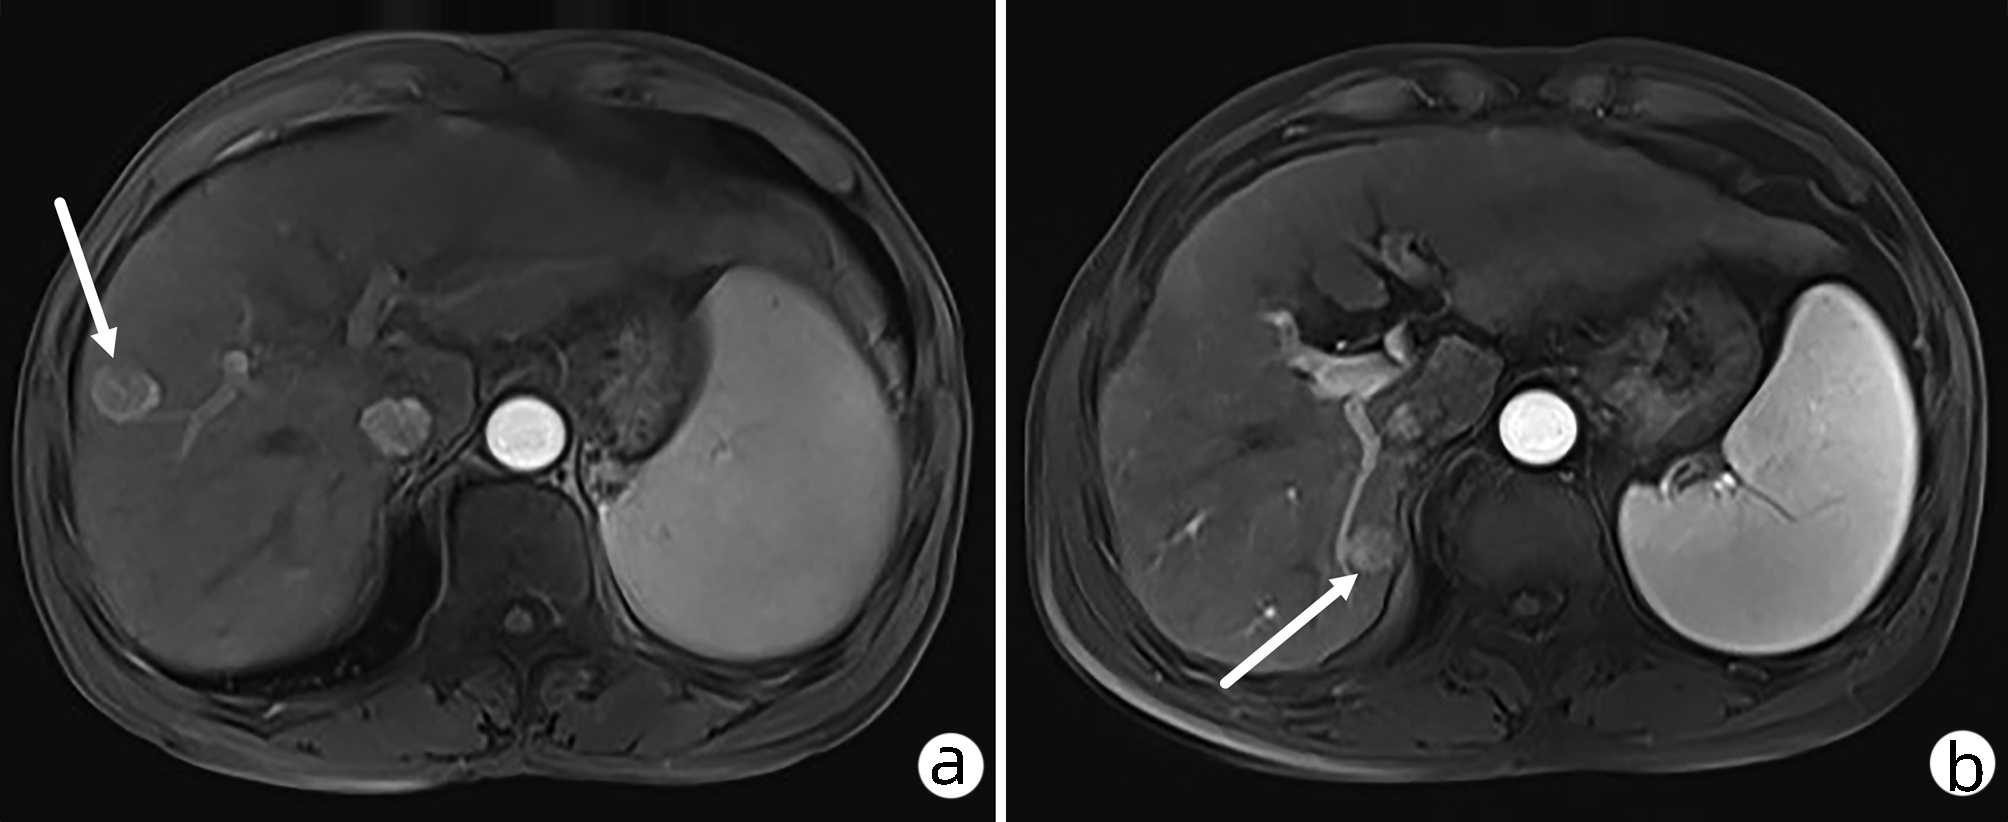

肝细胞癌合并胆管癌栓1例报告

鲁人竭, 孙芳芳, 杜杰, 赵丽荣

2022, 38(8): 1872-1874. DOI: 10.3969/j.issn.1001-5256.2022.08.028

摘要(801) HTML (455) PDF (3665KB)(82)